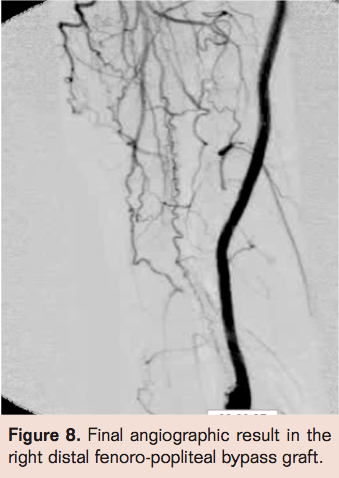

- Laser thrombectomy at 1 mm/sec. with the 2.3 mm probe (Figures 4-9)

Findings

Complete angiographic resolution of thrombus and definitive therapy was achieved in 51 of 78 patients (65.3%) during the index angiographic procedure in the angiographic suite. In 12 of 78 patients (15.3%) flow was established in the index procedure but there was residual thrombus necessitating continued lytic infusion. Of those 12 who had residual thrombus, 11 had complete resolution of thrombus following 3 hours of lytic therapy allowing definitive therapy in the same day. No flow was established during the index procedure for 15 of 78 patients (19.2%). Of these patients angiography via the side hole perfusion catheter showed substantial resolution of thrombus but enough residual thrombus to obstruct antegrade flow in 14 of 15. There was no evidence of thrombus resolution in 1 of 15 patients for whom no flow was established in the index procedure. Of those 15 patients,3 (20%) had complete resolution of thrombus at 3 hours post angiography while 12 of 15 patients (80%) required prolonged lytic infusion. Graft patency was established in 78 of 78 patients but bleeding complications were much less common in the group with successful index procedure than those requiring overnight infusion (2% vs 47% with major bleeding necessitating transfusion of 2 units of PRBC’s in 2 patients who had overnight lytics).